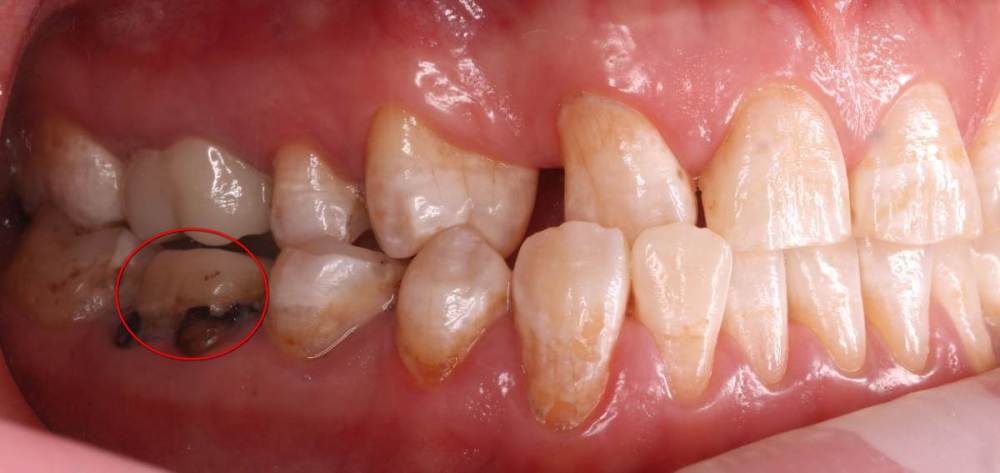

Роман1982 Опубликовано 25 мая, 2021 Поделиться Опубликовано 25 мая, 2021 Добрый день! Очень хотелось бы услышать объективное мнение специалистов. 40 лет На верхней челюсти от рождения не хватает двух резцов (12 и22) Перекрестный прикус В принципе, особо не беспокоит, хотя есть щелчки в суставе слева, если широко открывать челюсть. Из-за неправильно проводимого ранее лечения, встал вопрос об удалении в ближайшее время 25 и 26 зуба сверху и 46 снизу (на фото обведены красным). Ортопед рекомендовал пройти ортодонтическое лечение, т.к. в противном случае в дальнейшем могут возникнуть сложности с имплантами и коронками, может ухудшиться ситуация с суставом. Вот пытаюсь взвесить все за и против. Понимаю, что прикус было бы желательно исправить. Но! При текущем состоянии зубов не навредит ли это им еще больше? Исправление прикуса повлечет за собой необходимость установки на верхней челюсти еще двух дополнительных имплантов (на месте отсутствующих12 и 22). После исправления прикуса велика вероятность тотального протезирования. По словам того же ортопеда, может не хватить высоты сустава и тогда на все зубы понадобиться устанавливать коронки. Стоит ли затевать ортодонтическое лечение в данной ситуации или лучше не трогать то, что как-то функционировало 40 лет? Хотелось бы услышать аргументирование мнение. Ссылка на комментарий